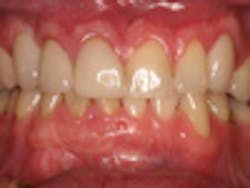

A 37-year-old male with a noncontributory medical history, taking no medications with no known food or drug allergies, presents to the office with a chief complaint of “I don’t like the way my upper right bridge looks.” His dental history includes extraction of tooth No. 6 two years ago due to a failed root canal and recurrent decay deemed restoratively hopeless. He was temporized one year after extraction with an acrylic bridge from teeth Nos. 5 to 7. Socially, he denied tobacco, drug, and alcohol use. The patient complained of color match, overcontoured bulkiness, and the inability to perform adequate oral hygiene.

One year post-insertion radiographs indicate that bone levels around the implant remain stable. Clinical results 1.5 years post-insertion reveal gingival levels to be stable and healthy, and the patient is very pleased with the esthetic result of his treatment.